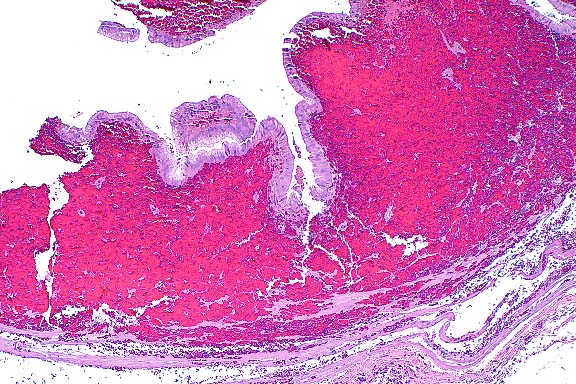

10x

obj

- Case 8-4. Kidney. Hematopoietic cells are largely

replaced by hemorrhage and congestion which expands the interstitium

and separates tubules.

40x

- Case 8-4. Kidney. Multifocally, tubular epithelium

is necrotic.

- Case 8-4. Multifocally and randomly throughout the

hepatic parenchyma, there are pale zones of hepatocellular necrosis

(loss of cell detail, karyolysis, pyknosis, & cell loss).